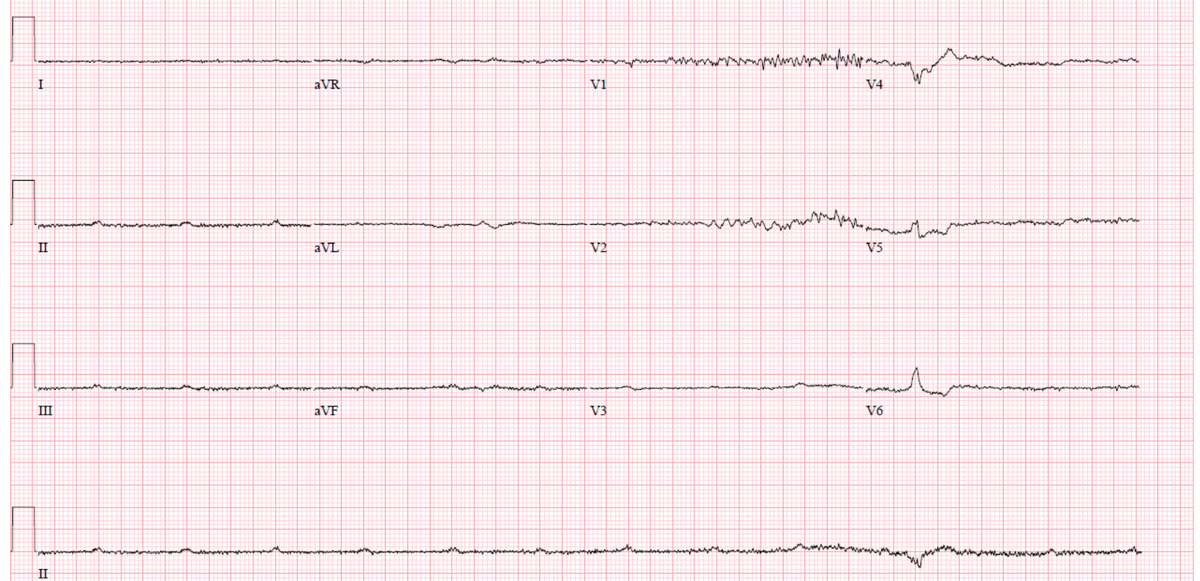

Kevin Brady@Hapa_EP·

The atypical flutters keep coming! Another interesting one with prior PVI. Where to burn #EPeeps?

72 yo m Severe AI s/p AVR, perm AF and high degree AVB. Sent for leadless. Found this. Tried HBP and no luck. Then moved the lead caudally. Narrower QRS when compared to RV pacing. Ideas? #EPeeps #dontdisthehis

Yoel Vivas tweet mediaYoel Vivas tweet mediaYoel Vivas tweet media